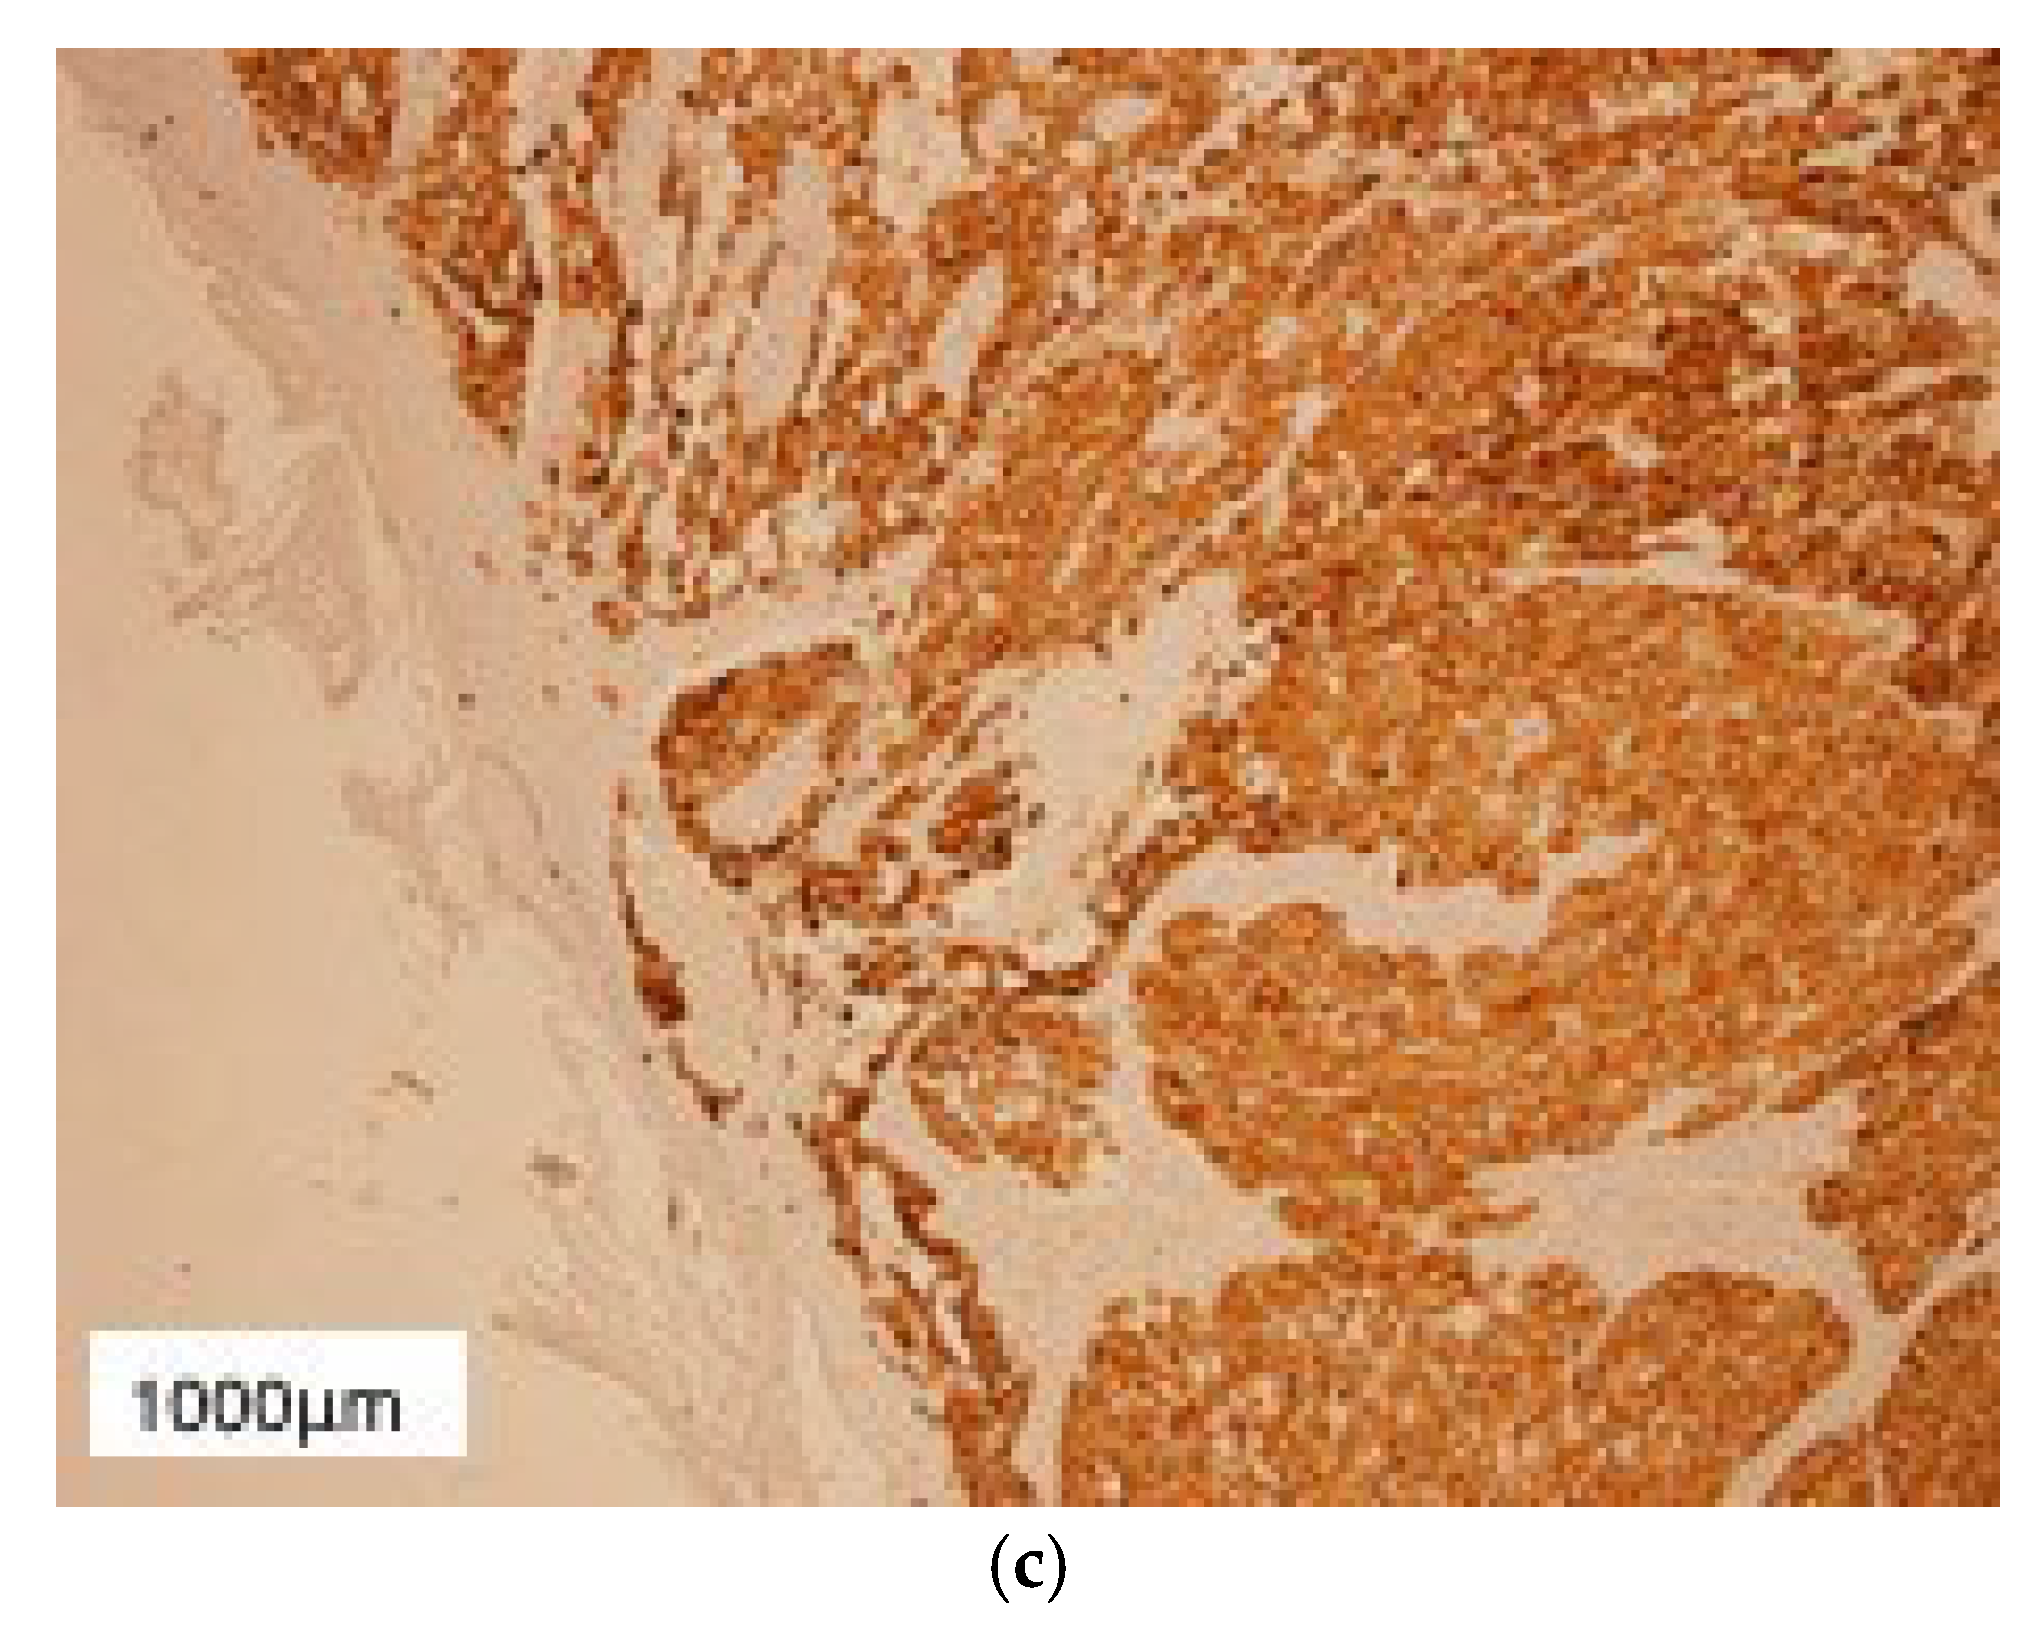

2. Case Presentation

3. Results